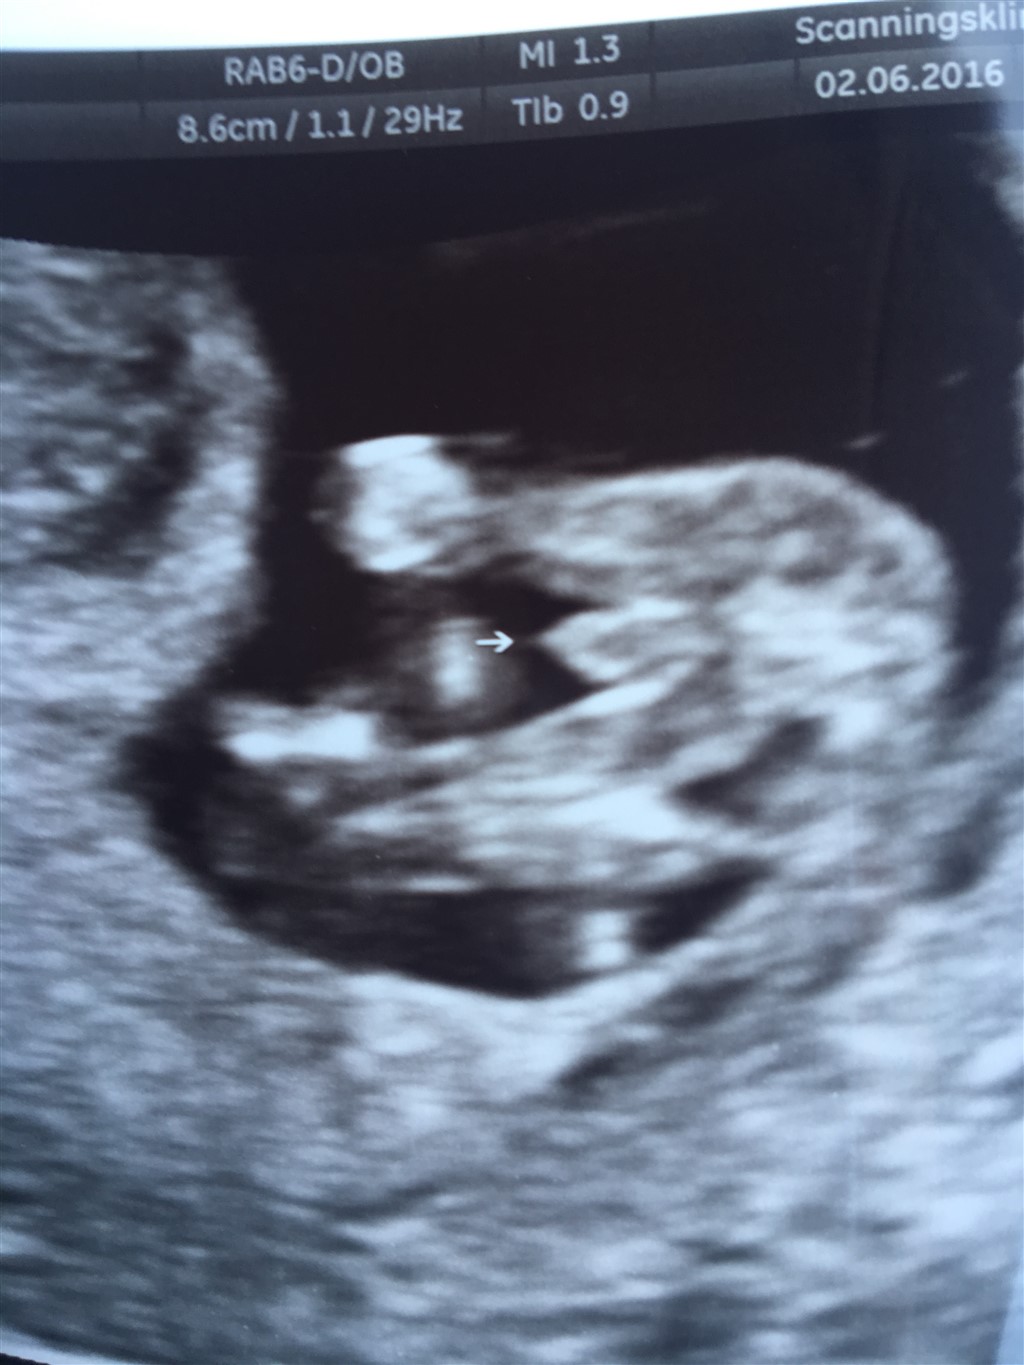

Scanningsdamen i dag var usikker på kønnet så vi skal komme igen om en uge. Hvad syntes i det ligner?

Ligner meget en dreng

men det er fordi de skal se det både nede fra og fra siden før de udtaler sig.. og fra siden skal man så ku se en tap der stritter op. Har lige lagt to billeder ind fra vores kønsscanning fra begge vinkler. Men udfra dit ene billede ligner det klart en dreng